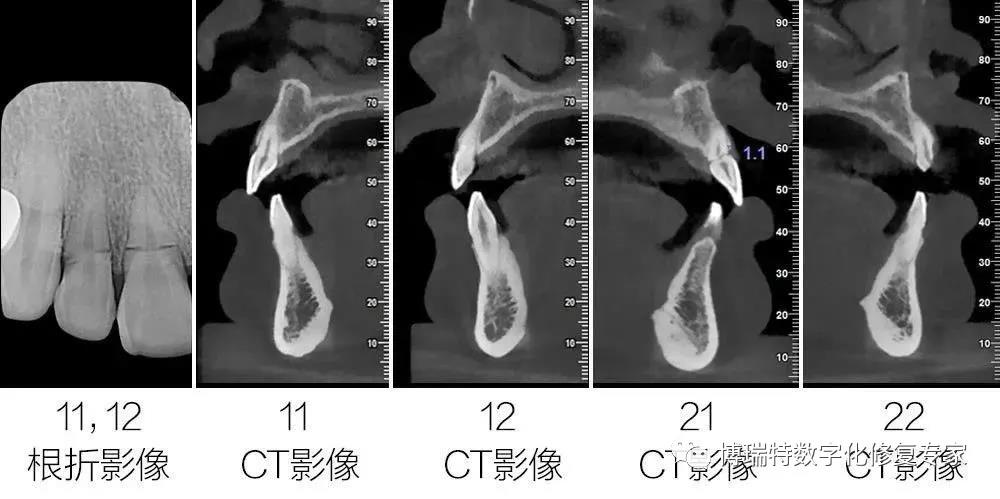

8226; CBCT检查显示11,12见根颈1/3根折线,无明显移位;

8226; 21根颈1/3根折,冠向移位,唇侧骨板完整,厚度约1mm,根尖区骨量充足;

8226; 22根长约9mm。

8226; 11、12和21根折;

8226; 22冠根折。